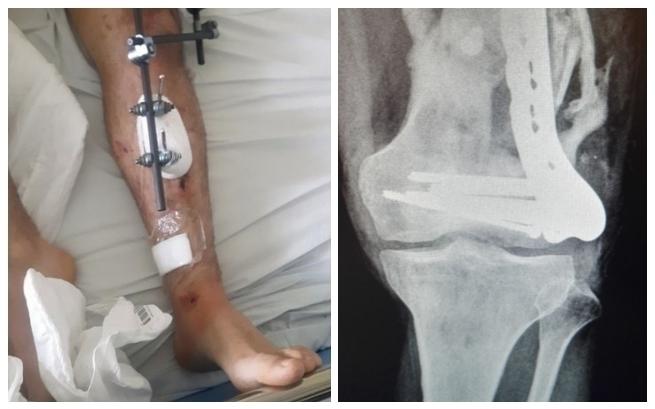

Trzy lata temu uległem groźnemu wypadkowi komunikacyjnemu. Doznałem wielu rozległych urazów i licznych złamań, usunięto mi śledzionę, uszkodziłem splot ramienny. Jedna chwila, która zmieniła moje życie – od tamtej pory nie mogę się swobodnie poruszać, a brak władzy w lewej ręce sprawia mi problemy w podstawowych czynnościach życiowych. Przez całe życie starałem sobie dawać radę z problemami sam, starałem się pomagać innym, teraz sam jestem zdany na pomoc. W tak młodym wieku utraciłem swoją sprawność...

Niedawno dowiedziałem się o konieczności przeprowadzenia operacji wstawienia endoprotezy stawu kolanowego. Przez wypadek cały staw jest zdeformowany, przez co mam bardzo ograniczone ruchy w kolanie i nieustannie odczuwam ogromny ból. Potrzebna jest operacja polegająca na wycięciu zdeformowanego stawu i wstawieniu sztucznego. Niestety implanty potrzebne do rekonstrukcji kolana są nierefundowane, ponieważ są wykonywane indywidualnie – tak, aby odzyskać jak największą sprawność kończyny. Operację można wykonać praktycznie w kilka tygodni, lecz koszt takiej operacji jest ogromny i przekracza moje możliwości.

Do tej pory przeszedłem wiele skomplikowanych operacji. Udało mi się wygrać walkę o życie, a teraz z każdym kolejnym dniem walczę o powrót do zdrowia. Byłem osobą zdrową i aktywną. Teraz nie mogę normalnie żyć. Pomóż mi, proszę, w walce o moje zdrowie...